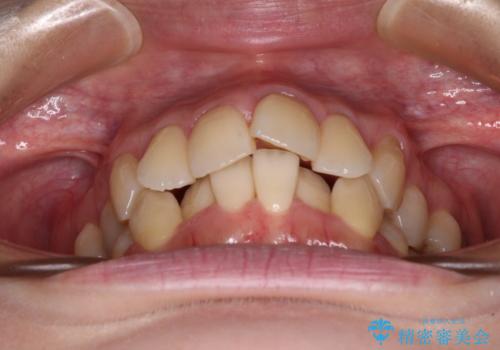

【モニター】急速拡大装置 狭い歯列を拡大してワイヤー装置で短期間治療

1. 開始前

1. 【モニター】急速拡大装置 狭い歯列を拡大してワイヤー装置で短期間治療の治療前